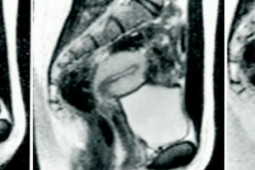

Chụp cộng hưởng từ (CHT hay MRI) là một kỹ thuật ghi hình ảnh sử dụng từ trường mạnh và sóng radio để tạo nên những hình ảnh của các cơ quan và cấu trúc bên trong cơ thể. MRI không sử dụng phóng xạ ion hóa (không dùng tia X)

Chụp hình MRI là một kỹ thuật không đau, không cần tới thuốc mê. Đối với trường hợp đặc biệt (người bệnh kích động, trẻ nhỏ, bệnh nhân không tự chủ được…) có thể phải dùng an thần hay gây mê. Ảnh minh họa: Internet

Chụp hình MRI là một kỹ thuật không đau, không cần tới thuốc mê. Đối với trường hợp đặc biệt (người bệnh kích động, trẻ nhỏ, bệnh nhân không tự chủ được…) có thể phải dùng an thần hay gây mê.